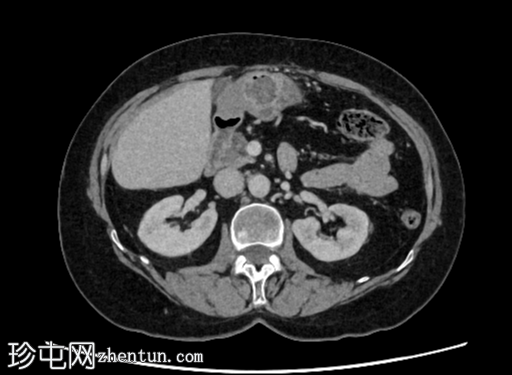

已知乳腺癌病例,随访CT扫描中偶然发现右肾外生性病变。

年龄:65岁

性别:女

轴位增强扫描(门静脉期)

右肾后上极可见2.8 cm外生性强化病灶,提示肾细胞癌(RCC)。右肾静脉和下腔静脉通畅。未见明显局部淋巴结肿大。右肝叶可见高密度金属影。可见含脂肪的脐疝。

右肾部分切除术后病理检查显示为嫌色细胞肾细胞癌。